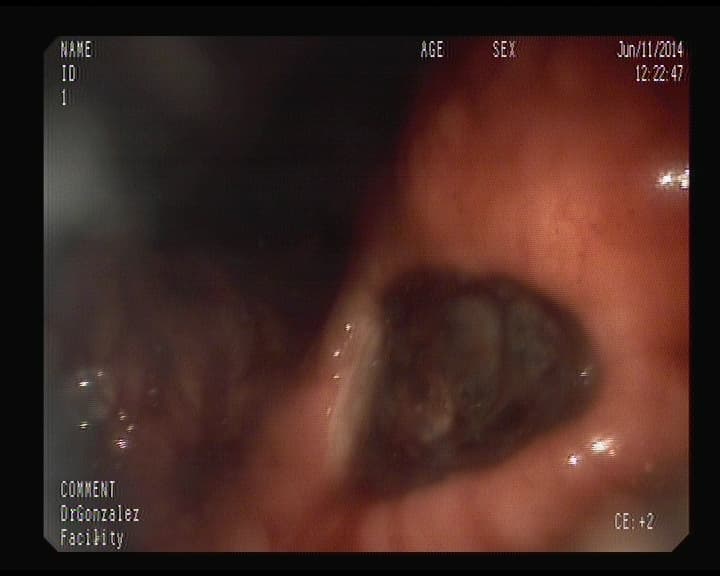

Crohn afectación del Ileon Terminal.

La imagen muestra ulceración rigidez, estrechez nodulaciones, por Enfermedad de Crohn, cuya causa se desconoce, y pudiera afectar cualquier punto del desde esófago hasta el ano, si bien lo más frecuente es afectación del intestino delgado, en Ileon terminal y el intestino grueso por segmentos.